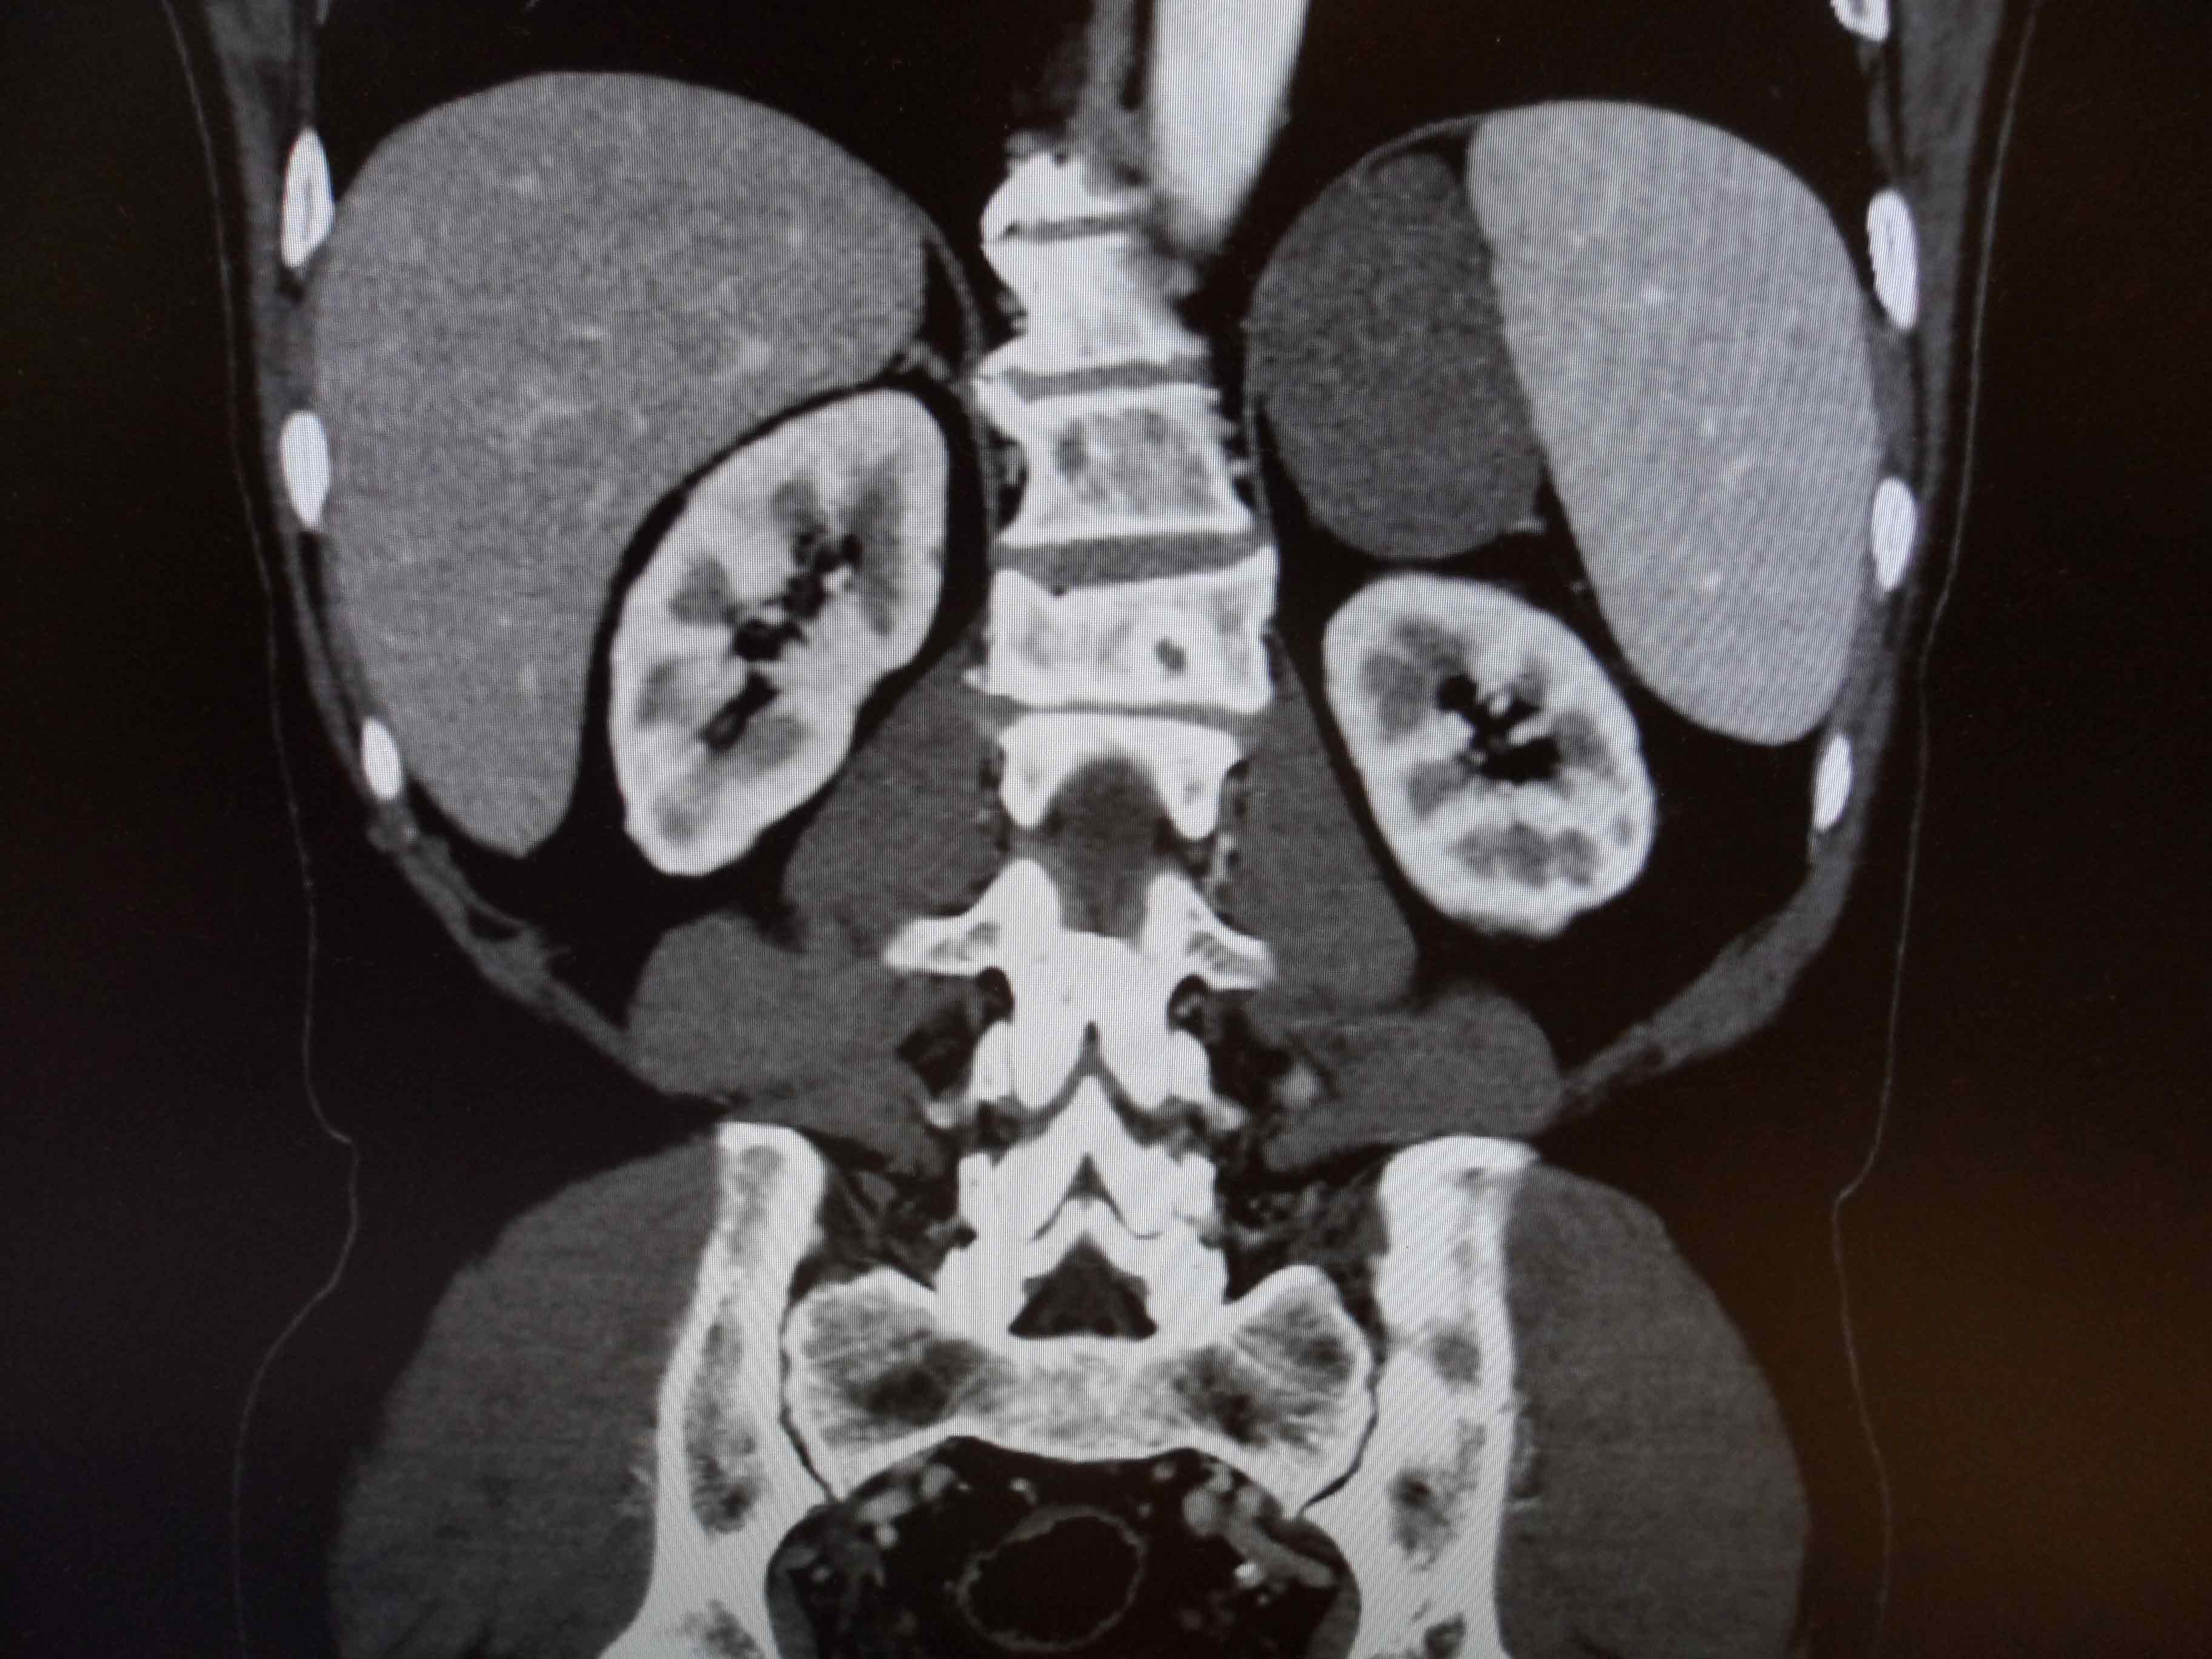

»çÁøCT/MRI

ºÎ½Å Á¾¾ç